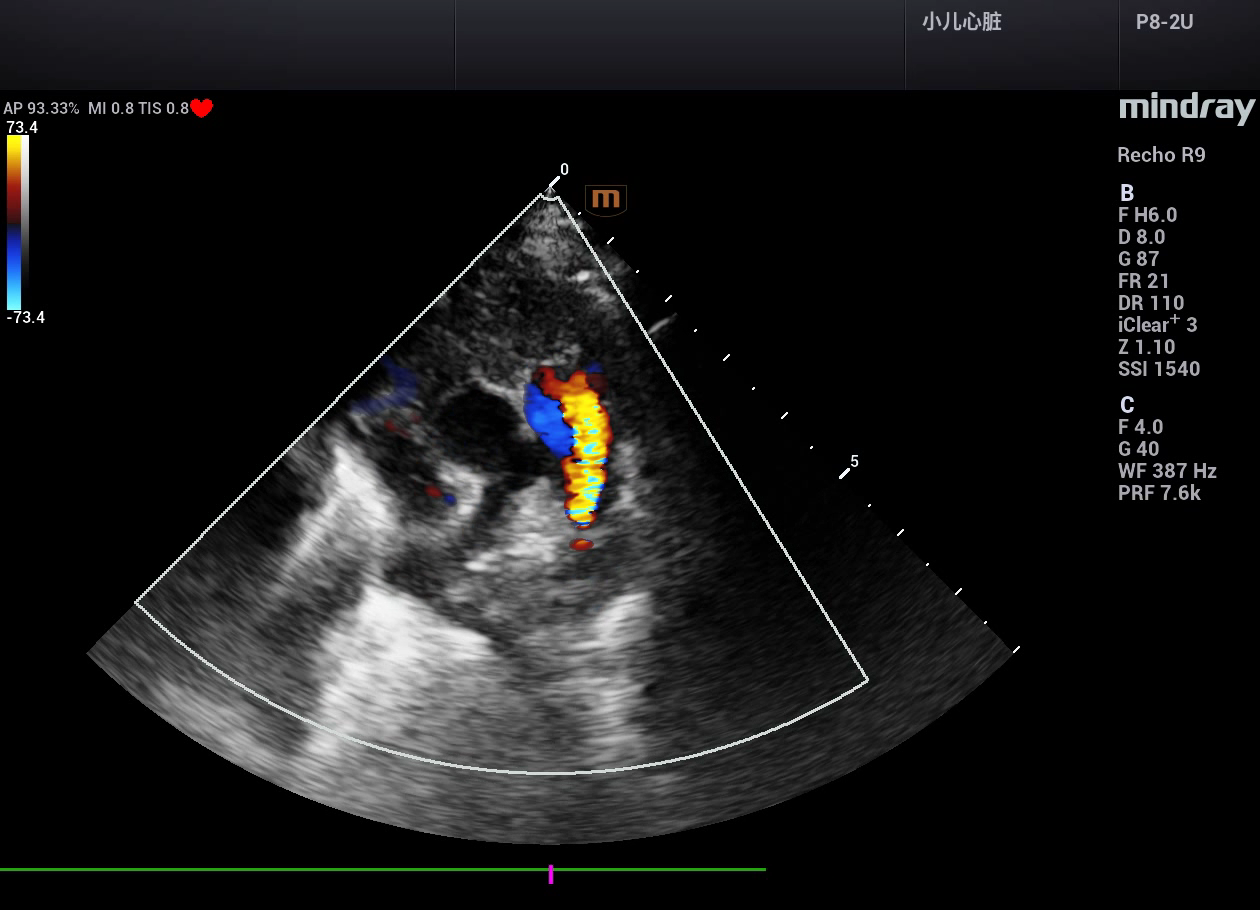

病例,婴儿动脉导管未闭(PDA),迈瑞Recho R9,2024年3月

病例,婴儿动脉导管未闭,迈瑞Recho R9,2024年3月。